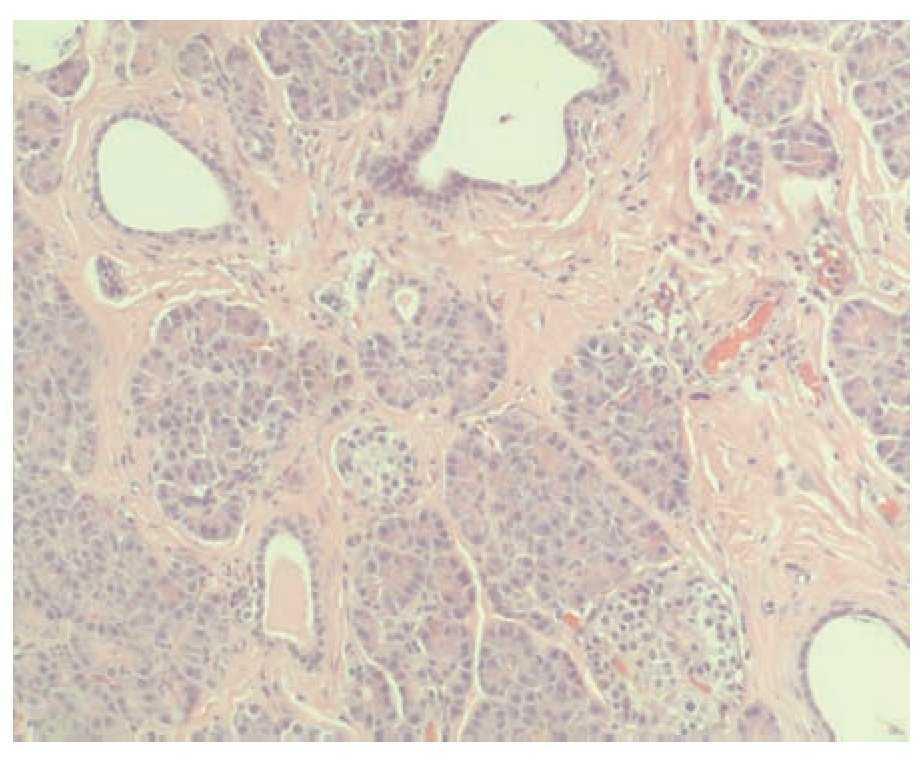

Hombre de 47 años de edad, sin antecedentes familiares o personales relevantes, con padecimiento de un día de evolución con dolor abdominal generalizado, vómito de contenido gastrobiliar y constipación. A la exploración física se encontró con FC 110 x', temperatura 38.5 °C, distensión abdominal importante, disminución de la peristalsis y signo de rebote presente. En los exámenes de laboratorio se encontró leucocitos de 10 700 / mm3, neutrofilia de 82% y bandemia de 7%. El paciente presentó deterioro clínico, con mayor distensión y dolor abdominal por lo que se decidió operarlo con diagnóstico probable de obstrucción intestinal. Se realizó laparotomía exploradora, encontrando torsión de un divertículo de Meckel ubicado a 60 cm de la válvula ileocecal, de 11 cm de longitud y 5.5 cm de diámetro, con pared de 0.3 centímetros de grosor (Figuras 1 y 2). Se encontraron datos de sufrimiento intestinal por lo que se realizó resección y anastomosis termino-terminal. En el examen microscópico, se observó un divertículo verdadero cubierto por mucosa normal del íleon, alternando con zonas de mucosa gástrica heterotópica (Figura 3). Las glándulas gástricas se encontraban rodeadas por linfocitos. En el fondo del divertículo se observó tejido pancreático heterotópico, compuesto por ductos, acinos e islotes de Langerhans de características histológicas normales (Figura 4). El paciente presentó evolución clínica satisfactoria en el postoperatorio y egresó sin complicaciones.

¿ Figura 4. En el fondo del divertículo, se observó tejido pancreático heterotópico, compuesto por ductos, acinos e islotes de Langerhans de características histológicas normales.